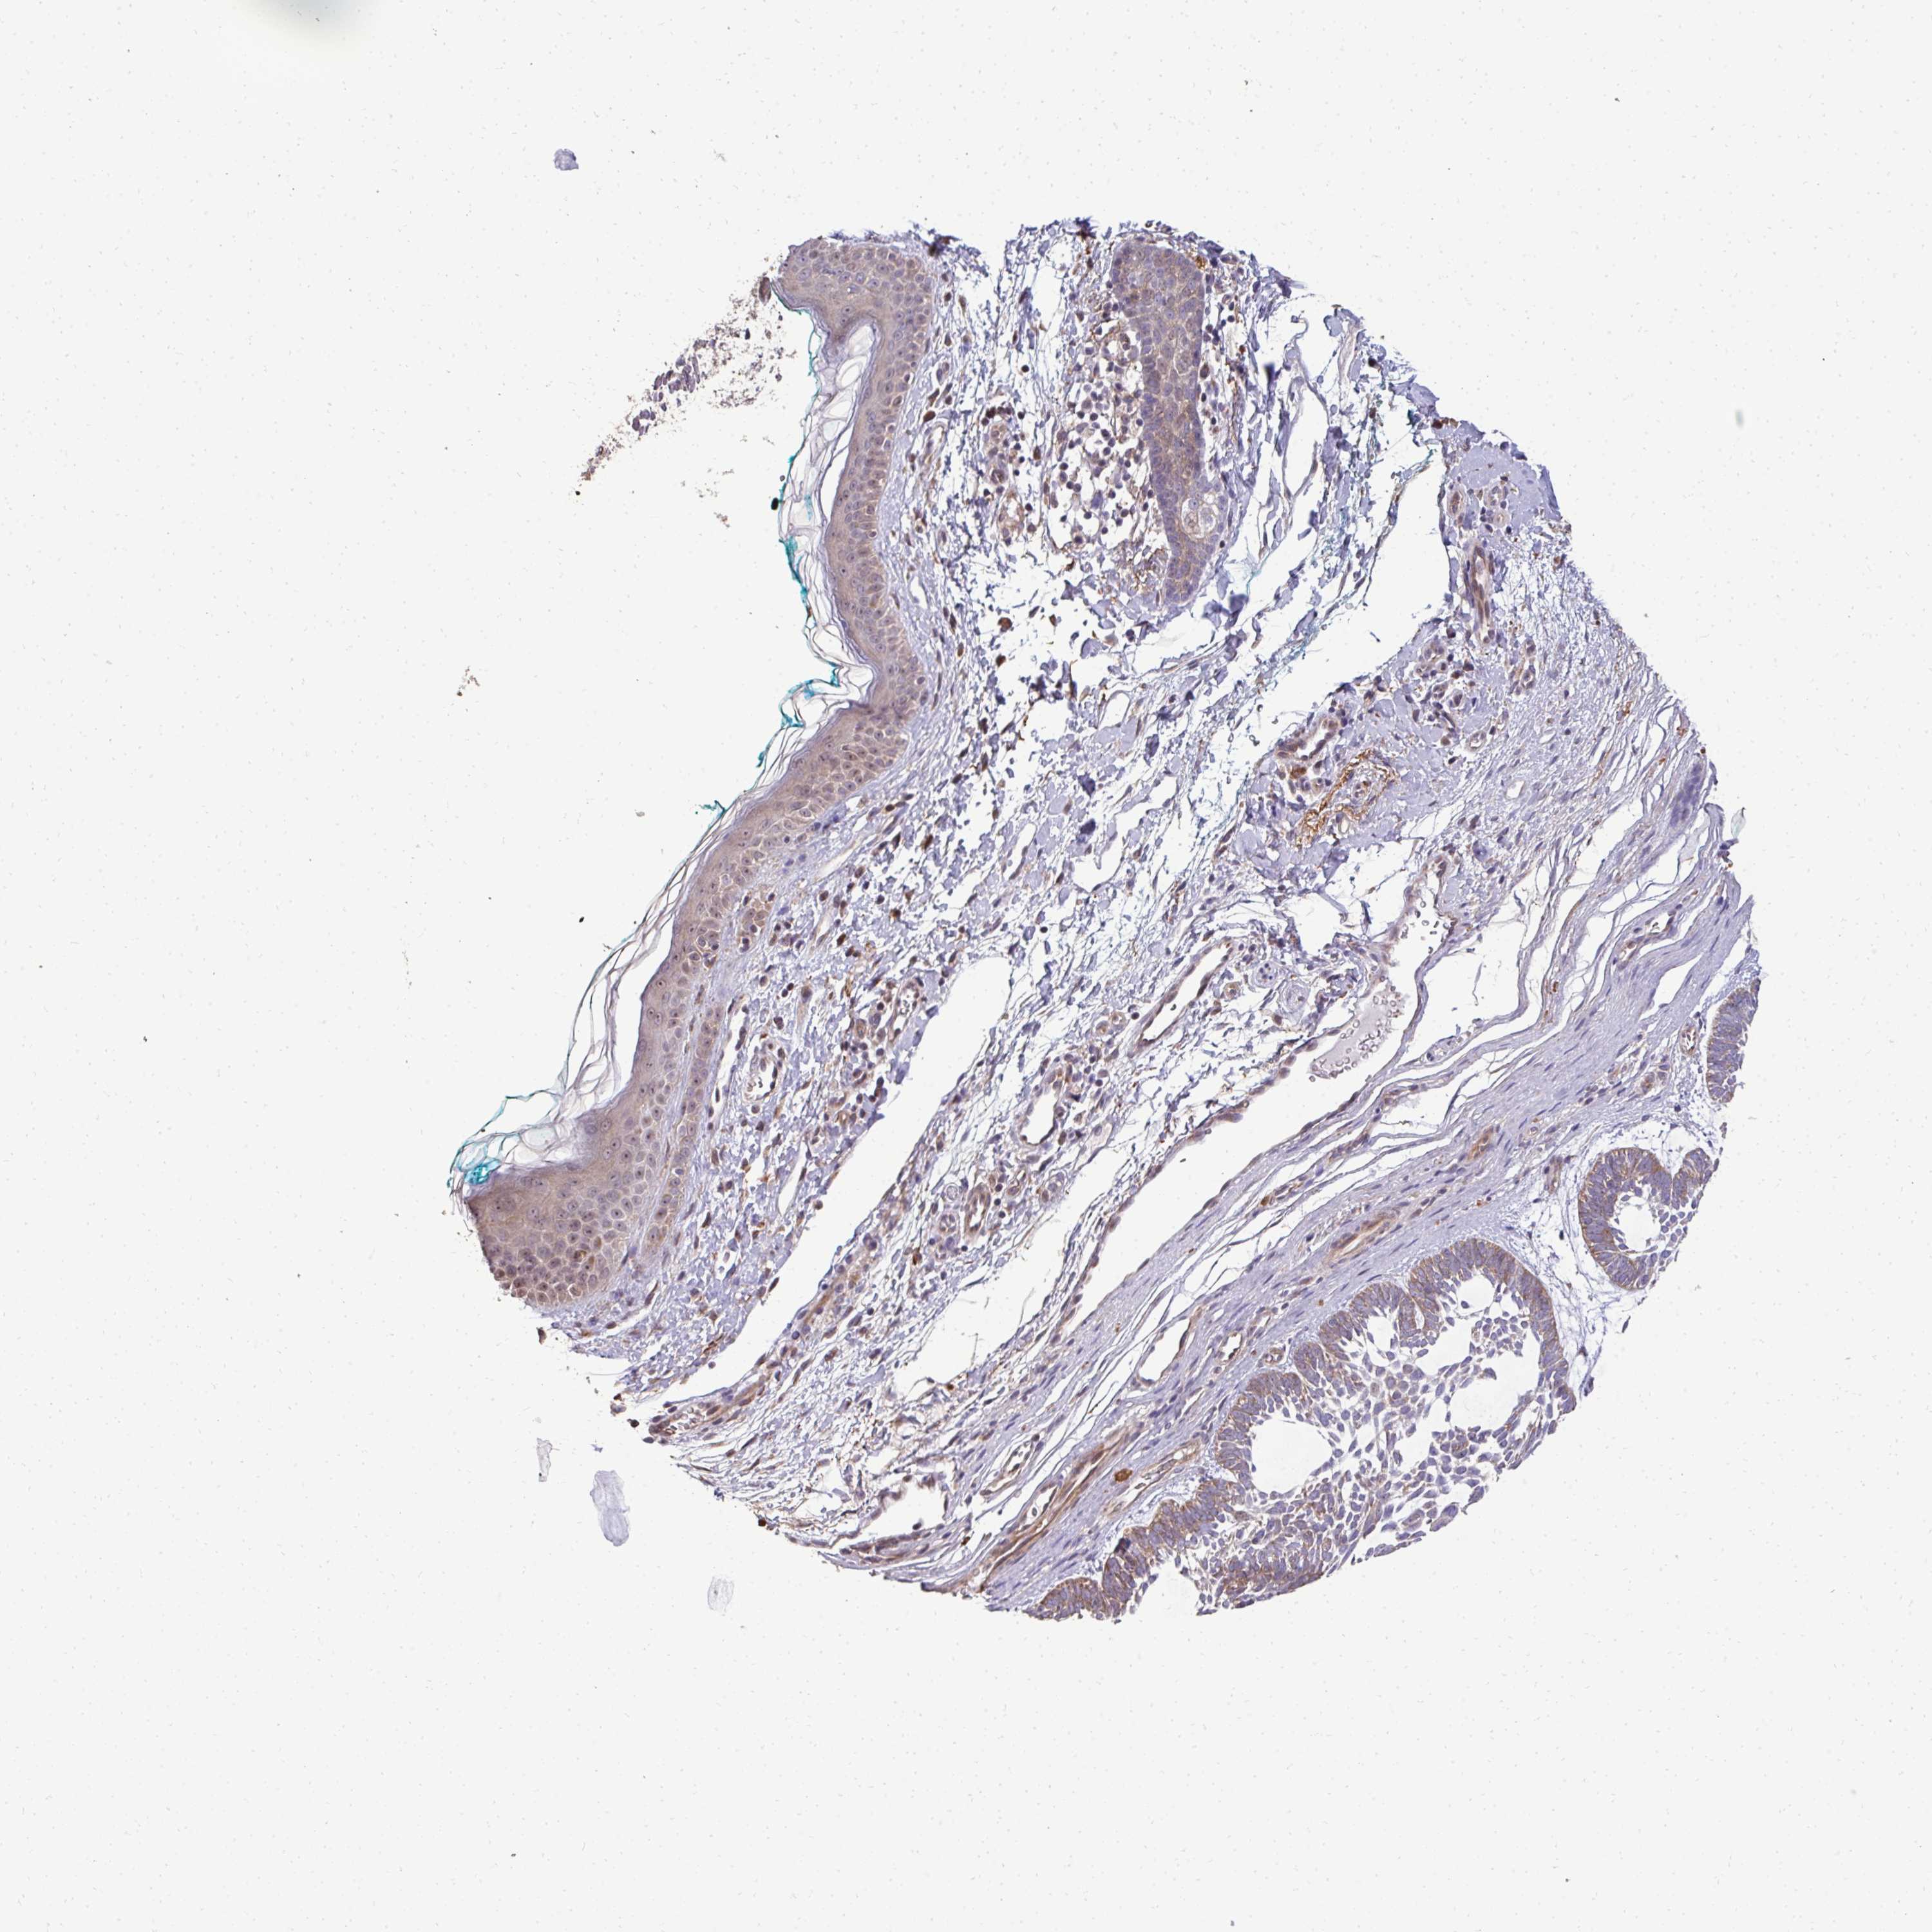

CANCER SKIN CANCER Show tissue menu

Basal cell and squamous cell cancer

SKIN CANCER - Protein expressioni

A mouse-over function shows sample information and annotation data. Click on an image to view it in a full screen mode. Samples can be filtered based on level of antibody staining by selecting one or several of the following categories: high, medium, low and not detected. The assay and annotation is described here.

Each image is clickable and will lead to virtual microscopy that enables deeper exploration of all samples and also displays staining intensity scores, fraction scores and subcellular localization as well as patient and tissue information for each sample.

Antibody HPA055353

Staining

High

Medium

Low

Not detected

Intensity

Strong

Moderate

Weak

Negative

Quantity

>75%

75%-25%

<25%

None

Location

Nuclear

Cytoplasmic/membranous

Cytoplasmic/membranous,nuclear

Basal cell carcinoma

Squamous cell carcinoma, NOS